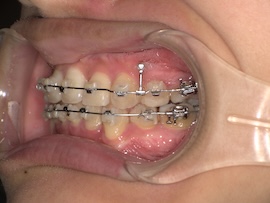

前回から1ヶ月後の歯並びはこんな感じです。

そこから1ヶ月後、